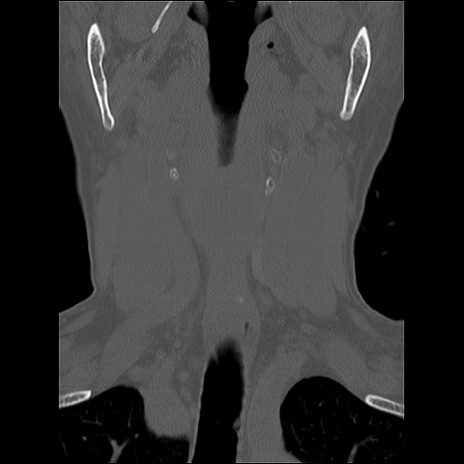

症例48 頚椎CT(冠状断像)

頚椎CT